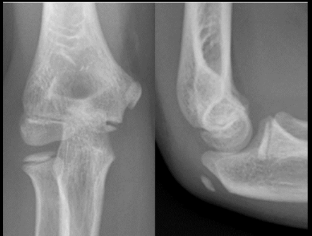

What findings are present?

A distal humerus fracture (e.g., supracondylar fracture in children or intercondylar fracture in adults) with posterior displacement of the distal fragment. This is a critical finding in trauma evaluations.

What does it mean when the elbow fat pads are visible?

bleeding! Likely due to a fracture.

What findings are present?

Fat pad signs- Fracture of radial head